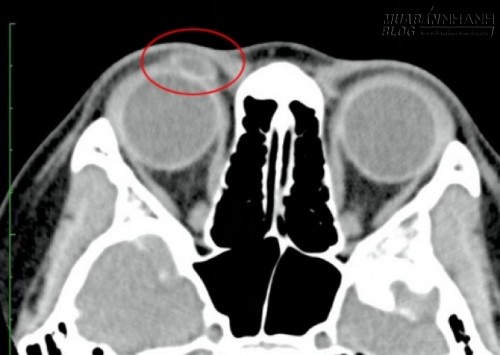

Tại đây, bản chụp CT đôi mắt tìm thấy một vết thương trên mí mắt do một vật cạnh cứng và cũng đã được lấp đầy bởi chất lỏng. điều này làm cho các bác sĩ tin rằng có một u nang trên mắt phải của cô.

Bản chụp CT mắt phát hiện có vật cứng trong mắt cô bé.